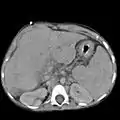

Ultrasound is routinely used in the evaluation of cirrhosis. It may show a small and nodular liver in advanced cirrhosis along with increased echogenicity with irregular appearing areas. Other liver findings suggestive of cirrhosis in imaging are an enlarged caudate lobe, widening of the fissures and enlargement of the spleen. An enlarged spleen (splenomegaly), which normally measures less than 11–12 cm in adults, can be seen and may suggest underlying portal hypertension. Ultrasound may also screen for hepatocellular carcinoma, portal hypertension, and Budd-Chiari syndrome (by assessing flow in the hepatic vein). An increased portal vein pulsatility is an indicator of cirrhosis, but may also be caused by an increased right atrial pressure.[33] Portal vein pulsatility can be quantified by pulsatility indices (PI), where an index above a certain cutoff indicates pathology:

Other tests performed in particular circumstances include abdominal CT and liver/bile duct MRI (MRCP).